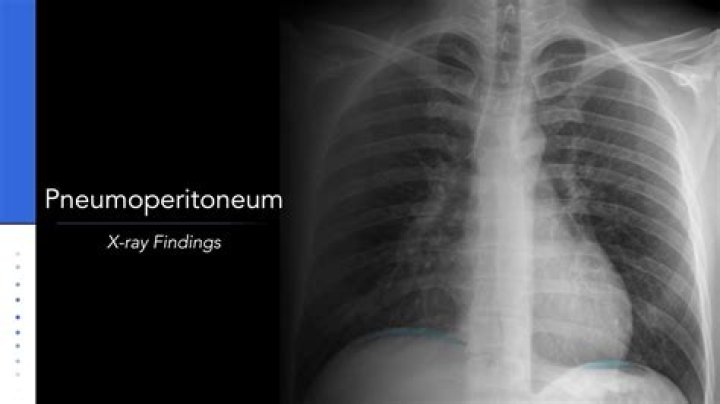

Is pneumoperitoneum fatal

Pneumoperitoneum is a medical emergency, which is defined as the presence of free air within the peritoneal cavity.

Is pneumoperitoneum a diagnosis?